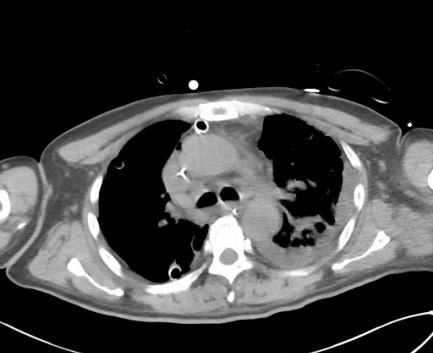

图片

▲治疗第5天颈部(冠状位),胸部(轴位)